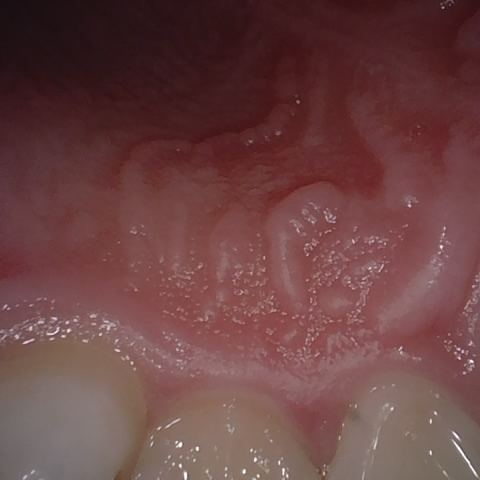

Image 1070 / 1535

NHD39990

Annotated as "Good"

Original Image Rendering Image